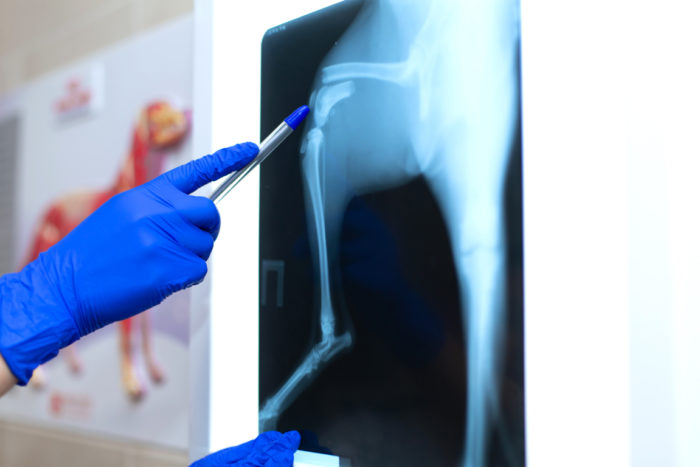

Diagnòstic per imatge

El diagnòstic radiològic és molt important en el dia a dia de la clínica veterinària per a la realització d’un correcte diagnòstic de molt diverses patologies. Disposem de sistemes de radiologia digital d’alta qualitat.

L'Arca Clínica Veterinària Lleida